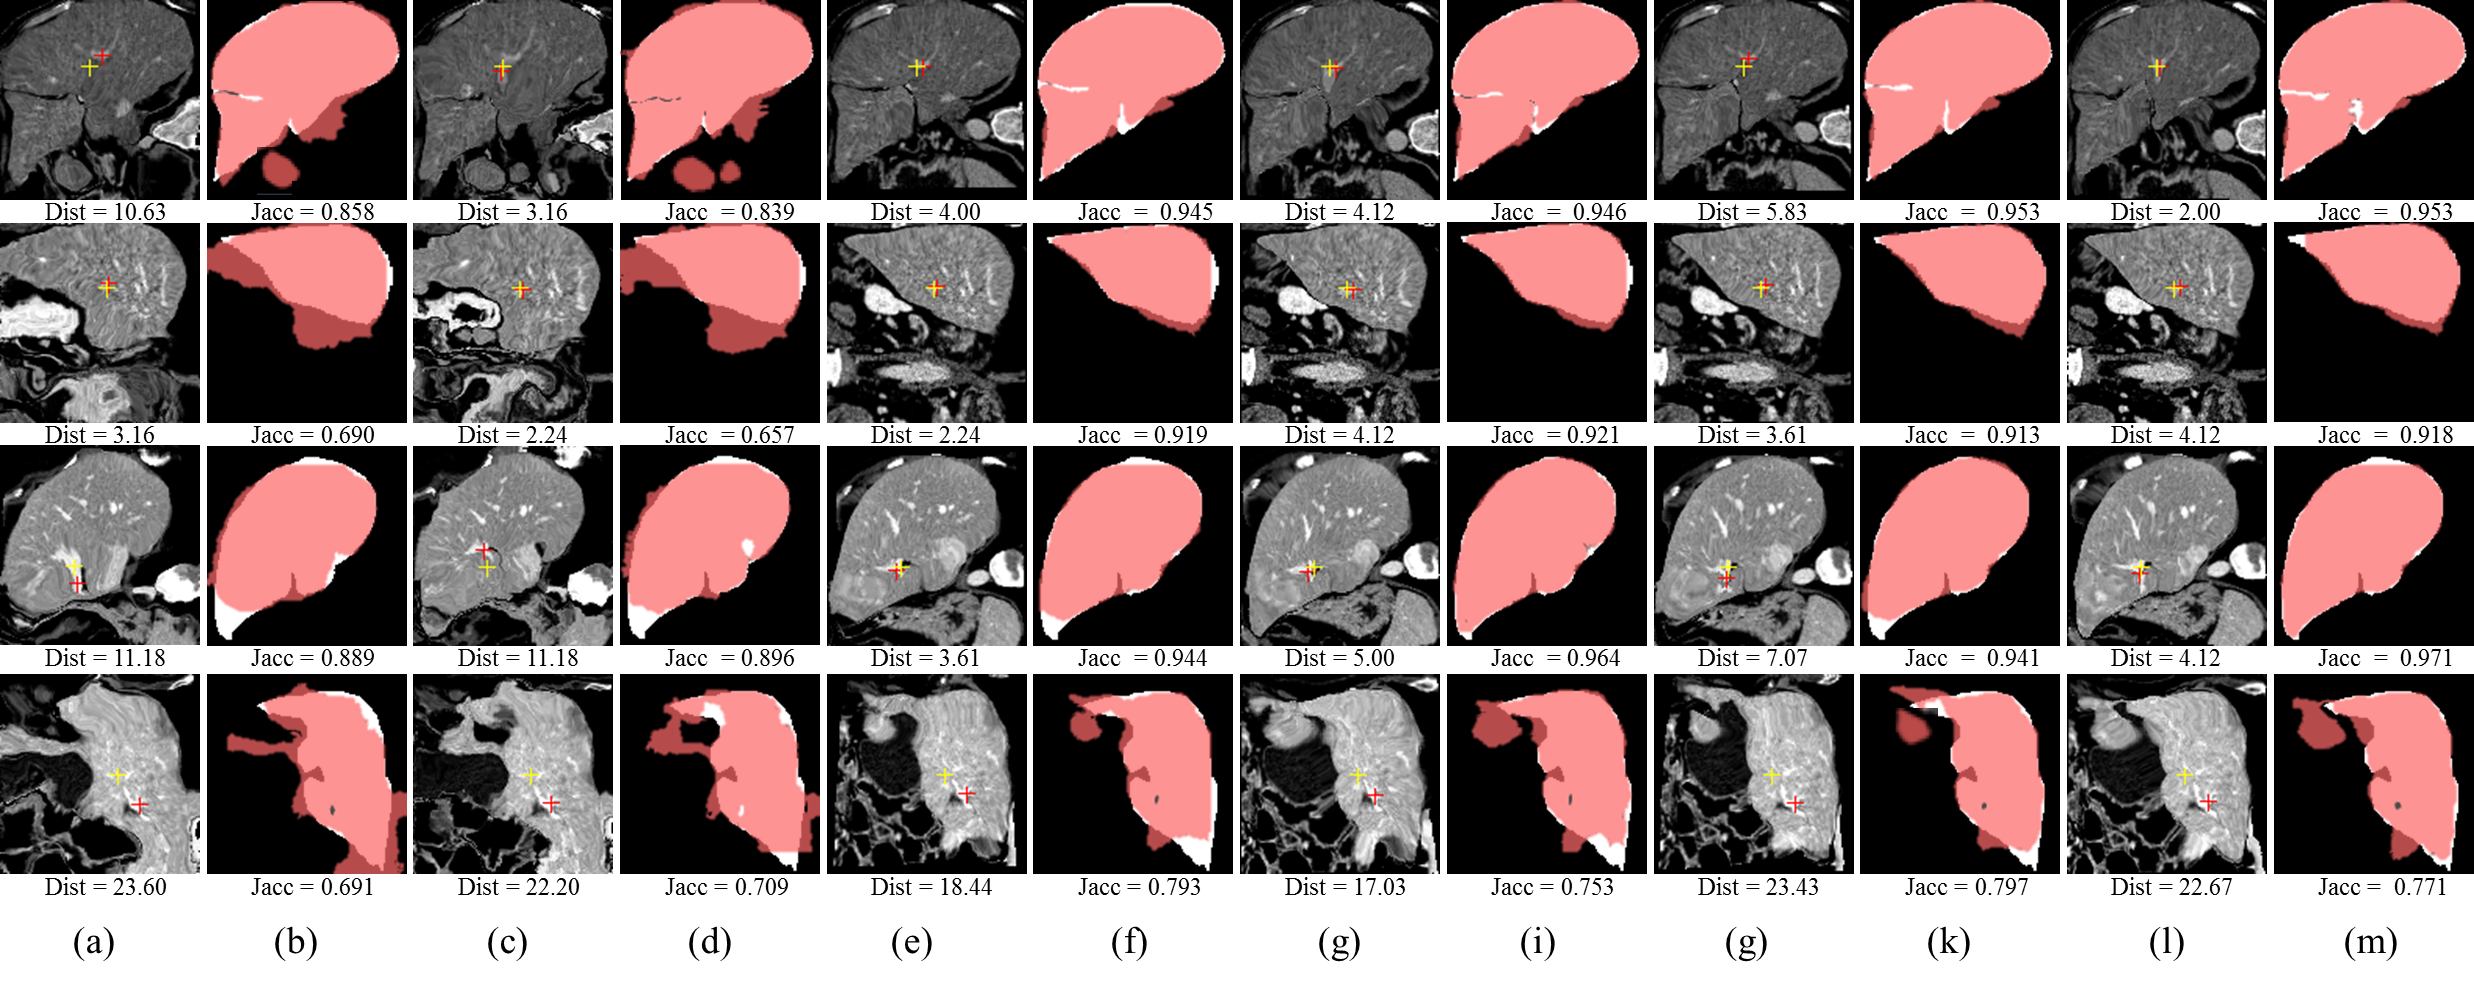

IV-G Experiments on CT Liver Registration

The 3D liver CT dataset is provided by the MICCAI 2007 Grand Challenge [48], which consists of images from 20 subjects. We discard two anomalous subjects and select the remaining 18 subjects. This dataset only provides ground-truth segmentation masks, and the coordinates of the landmarks are manually annotated by three doctors. Four landmarks (L1, L2, L3, L4) on the liver portal vein are selected (see Figure 6). Each doctor labels the coordinates of the landmarks separately in 3D volumes via the ITK-SNAP tool. The average coordinates from the three doctors are considered the ground-truth positions of the landmarks. The regions of interest (128×\times128×\times128 voxels) containing the liver are extracted for further processing. As our network currently only supports 2D input images, we slice 3D CT volume along three orthogonal axes. Affine transformation (implemented by ANTs with mutual information as the metric) is applied to each 3D CT image before we slice 3D volume into 2D images. During the training phase, a pair of slicing planes A and B at the same position of the CT volumes are interchangeably treated as a pair of fixed and moving images. This procedure produces a total of 117,504 (18×\times17×\times3×\times128, 18×\times17 subject pairs, 3 directions and 128 positions) 2D images for training and evaluation.

Refer to caption

Figure 6: This sketch illustrates the landmarks selected in the CT liver dataset. P1: hepatic portal, P2: superior branch of left lobe, P3: inferior branch of left lobe, P4: medial branch of left lobe, P5 and P8: anterior branch of right, P6: inferior branch of right lobe, P7: superior branch of right lobe. L1, L2, L3, L4 are the selected landmarks, where L1 is the intersection point of P6 and P7, L2 is the intersection point of P5 and P8, L3 is the intersection point of P6 and P7 and L4 is the first bifurcation point of left portal.

IV-G2 Experiment Results

Trifold cross validation is adopted in the experiment and the results are reported only on the 3,672 (18×\times17×\times4×\times3×\times1) 2D slice pairs containing the same corresponding landmarks. Table III quantitatively shows the performance of our unsupervised methods, our best baseline (supervised methods) and the best traditional registration algorithms. We retrain the unsupervised PN and PE model with this enlarged dataset and obtain an improvement on the registration performance. Notably, Dist of PE model decreases from 13.79 to 13.54 and Jacc increases from 0.837 to 0.845, as is shown in Table III. Figure 7 illustrates the registration results of different methods.

Figure 7: Illustration of the liver registration performance of the proposed unsupervised methods, our best supervised baseline (w/ mask) methods and one the best traditional registration algorithms (Elastix) with the best Dist: (a) Moving image, (b) Ground truth segmentation mask of moving image, (c) Fixed image, (d) Ground truth segmentation mask of fixed image. (e), (g), (i) and (k) respectively denote the moving images warped by the best traditional registration algorithm (elastix), our best supervised baseline method (itk16), our best unsupervised method PN. The translucent red masks in (f), (h), (j), (l) respectively correspond to (e), (g), (i), (k) and denote the warped ground truth segmentation mask of the moving images. The white masks in (f), (h), (j), (l) are the ground-truth segmentation mask of the fixed image. The red and yellow crosses denote landmarks of moving image and fixed image, respectively. Dist in (c) and Jacc in (d) denote no registration.

Table IV compares our baselines with several traditional registration algorithms. Our baselines run faster than traditional registration algorithms and achieve superior performance both in terms of Dist and Jacc.

Although our methods outperform traditional methods, the performance of liver registration is still far from clinical requirements. In order to enhance the accuracy of registration, we introduce ROI segmentation mask into our unsupervised pipeline as an extra component. The details of ROI segmentation mask are illustrated in supplement material.

As is illustrated in Table III, the performance of liver registration is beyond satisfying, which is far from clinical requirements. Thus, we add another extra experiment by introducing ROI segmentation module into the image-to-image deformable regsitration module. To demonstrate the contribution of the ROI segmentation module, we compare the performance of different models with the ROI segmentation module, denoted by w/ mask. Table V quantitatively shows the performance of our unsupervised methods with mask, our best baseline (supervised methods) and the best traditional registration algorithms with mask.

The unsupervised methods PMN w/ mask and PME w/ mask exhibit capability to align object boundaries by achieving high Jaccard Coefficient 0.903 and 0.905 respectively. And it’s evidenced that ROI segmentation mask has significantly increased the performance of liver registration both in Dist and Jacc. Notably, methods based on convolution neural networks achieve 100x speedup compared to traditional methods. Figure 7 illustrates the registration results of different methods on liver CT data.

Figure 9 illustrates the registration results of unsupervised methods w/ mask (in Table V) and without mask (in Table III).

Figure 9: Illustration of the liver registration performance of the proposed unsupervised methods with and without mask: (a), (c), (e), (g), (i) and (k) respectively denote the moving images warped by PN, PE, PE with more unlabeled data, PMN w/ mask and PME w/ mask, PME w/ mask with more unlabeled data. The translucent red masks in (b), (d), (f), (h), (j), (l) respectively correspond to (a), (c), (e), (g), (i), (k) and denote the warped ground truth segmentation mask of the moving images. The white masks in (b), (d), (f), (h), (j), (l) are the ground-truth segmentation mask of the fixed image. The red and yellow crosses denote landmarks of moving image and fixed image, respectively.